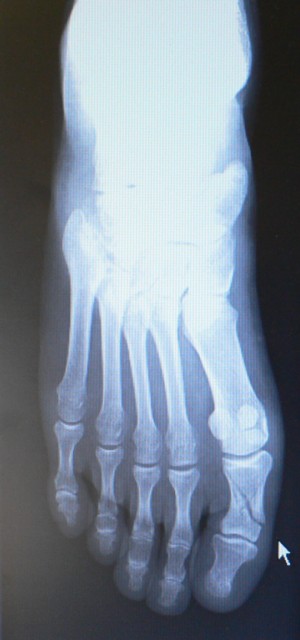

斜めに折れています。

他に小指の根元の方も2ヶ所折れています(レントゲン写真では見えにくい)

右1趾基節骨骨折・右足根骨多発骨折 が傷病名です。

前者(斜めに折れている部分)はピンで固定する手術が必要、

後者は放っておいていいとのこと。(ただし、動かないように固定)